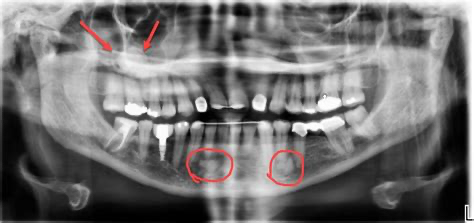

What Cancer Might Look Like on a Dental X-Ray

First, let’s set the stage: X-rays show contrast. Denser materials (like bone) appear light or white. Less dense materials (like soft tissue, air spaces, or fluid-filled cysts) appear darker. Dental X-rays excel at capturing the structural integrity of teeth and jawbone. They’re less helpful when it comes to soft tissue (we’ll tackle that later).

So what might a cancerous lesion look like on an X-ray?

- Irregular bone loss: Not the neat, horizontal resorption you see in gum disease, but patchy, asymmetric erosion—often described as “moth-eaten” or “ill-defined.”

- Radiolucent lesions: That means dark areas where you wouldn’t expect them. These can suggest anything from a cyst to a benign tumor to something more ominous like a malignancy.

- Loss of lamina dura: This is the thin, white line that outlines the tooth socket. If it’s missing or disrupted, that might be a red flag.

- Unusual widening of the periodontal ligament space: This can be a subtle but early sign of malignancy.

- Root resorption or displacement: When a tumor presses against or invades bone, it can alter the natural positions of roots and surrounding structures.

So yes—X-rays can absolutely pick up on abnormalities that raise concern for cancer, particularly when it involves bone invasion or deep-seated tumors in the jaws or sinuses.

Take the case of jawbone tumors, for instance—osteosarcomas, ameloblastomas, or metastatic lesions that have traveled from another primary cancer site (like breast or prostate). These are often first noticed on a routine X-ray when the dentist sees something that just doesn’t look right. Sometimes the finding is incidental: a patient comes in for wisdom teeth removal, and the panoramic X-ray reveals a mass in the mandible.

Or consider sinus involvement. A periapical or panoramic image might reveal opacification or bony destruction of the sinus floor—something a sinus infection wouldn’t typically cause. This can lead to further imaging, a referral to ENT, and ultimately, a diagnosis that might have otherwise been missed for months.